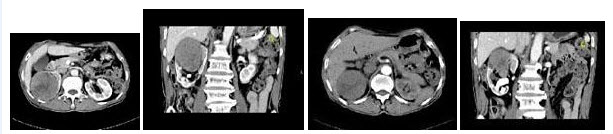

5、单项选择题

男,27岁,根据所示图像,最可能的诊断是()